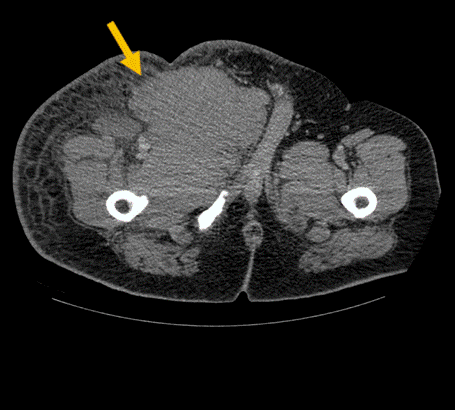

Se realiza tomografía computada de tejidos blando en la que se observa gran lesión con realce homogéneo del contraste que se extiende desde la región inguinal hasta la región anterior medial del muslo derecho proximal, asociado a cambios inflamatorios en tejidos blandos, de 20.2 x 10.5 x 15.2 cm en sus ejes longitudinal, antero posterior y transverso (Figuras 1 y 2).